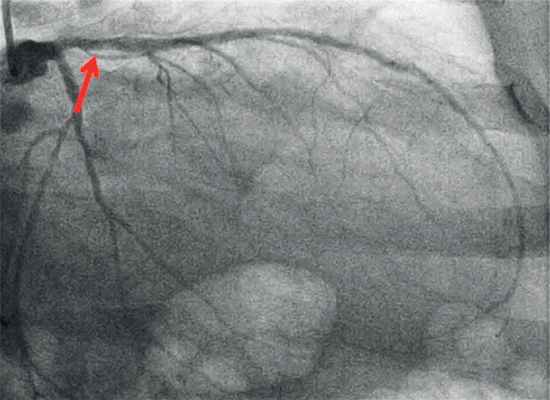

Консилиумом, состоящим из кардиологов, рентгенэндоваскулярных и сердечно-сосудистых хирургов, принято решение о проведении хирургического лечения. Перед операцией выполнена коронароангиография, выявлен стеноз 50% в устье передней нисходящей артерии (ПНА) (рис. 4).

Рис. 4. Коронароангиография пациента И.

Стеноз 50% в устье передней нисходящей артерии.